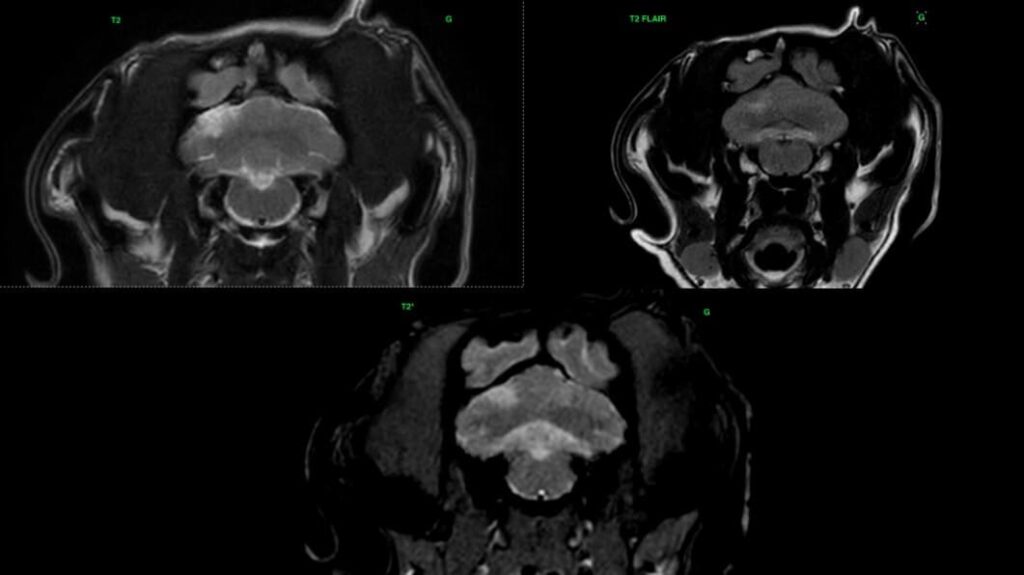

L’IRM est l’imagerie de choix pour ces lésions ischémiques. Les lésions aigues apparaissent hyperintenses sur les séquences T2 et T2 FLAIR, hypointense en pondération T1, et ne montrent pas de rehaussement. L’imagerie en diffusion permet une détection plus précoce de ces lésions. Elle permet également une estimation de l’âge de la lésion et de la taille du noyau infarcié. Les lésions aigues présentent une restriction du signal de diffusion, et apparaissent hyperintense sur la séquence DWI, et hypointenses sur la carte ADC. Les valeurs sur la séquence ADC sont diminuées pendant 4-5 jours, se normalisent entre 4 et 10 jours, et réaugmentent après 10 jours. Ces lésions ne créent pas d’effet de masse, sauf en cas d’œdème vasogénique associé, à son maximum 3-4 jours après l’apparition de la lésion. On peut parfois observer un rehaussement périphérique de la lésion pendant la phase de rupture de la barrière hématoméningée.

En phase chronique, le signal T2 reste stable, mais on observe une réduction progressive du signal en T2 FLAIR. Le signal est parfois mixte sur la séquence T2 FLAIR, en raison de la présence de zones hypointenses d’encéphalomalacie, et de zones hyperintenses de gliose. La taille des lésions diminue en phase chronique, avec atrophie du parenchyme cérébral. Le rehaussement éventuellement présent disparait lors de la restauration de la barrière hématoméningée.